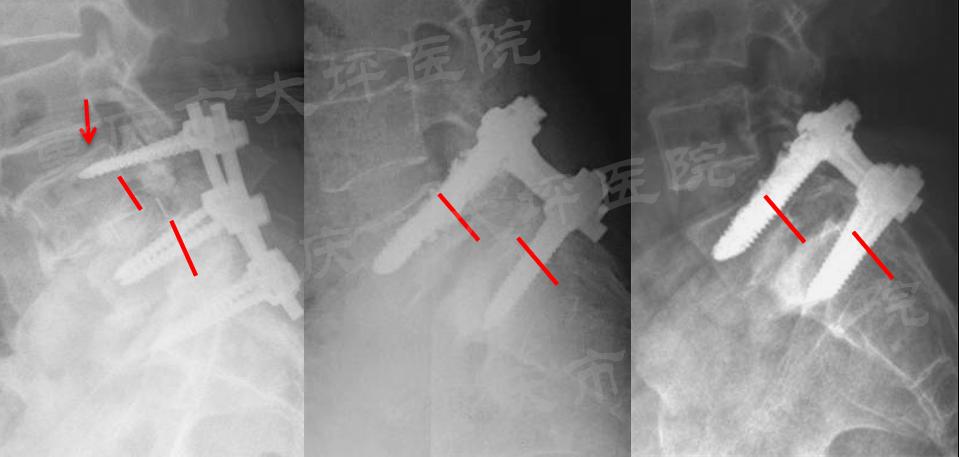

腰椎滑脱症是一种上位椎体相对于下位椎体向前滑移,以腰腿痛、间歇性跛行为主要症状的常见退变性脊柱疾病,成年人发病率约为6%。对于保守治疗无效的患者,采用后路椎弓根螺钉内固定技术复位滑移椎体、恢复腰椎序列、坚强固定达到骨融合是主要的治疗方式。然而,老年骨质疏松人群由于骨质疏松极大的降低了椎弓根螺钉的稳定性,极易发生内固定失败(图1)。

图1:腰椎滑脱内固定失败病例